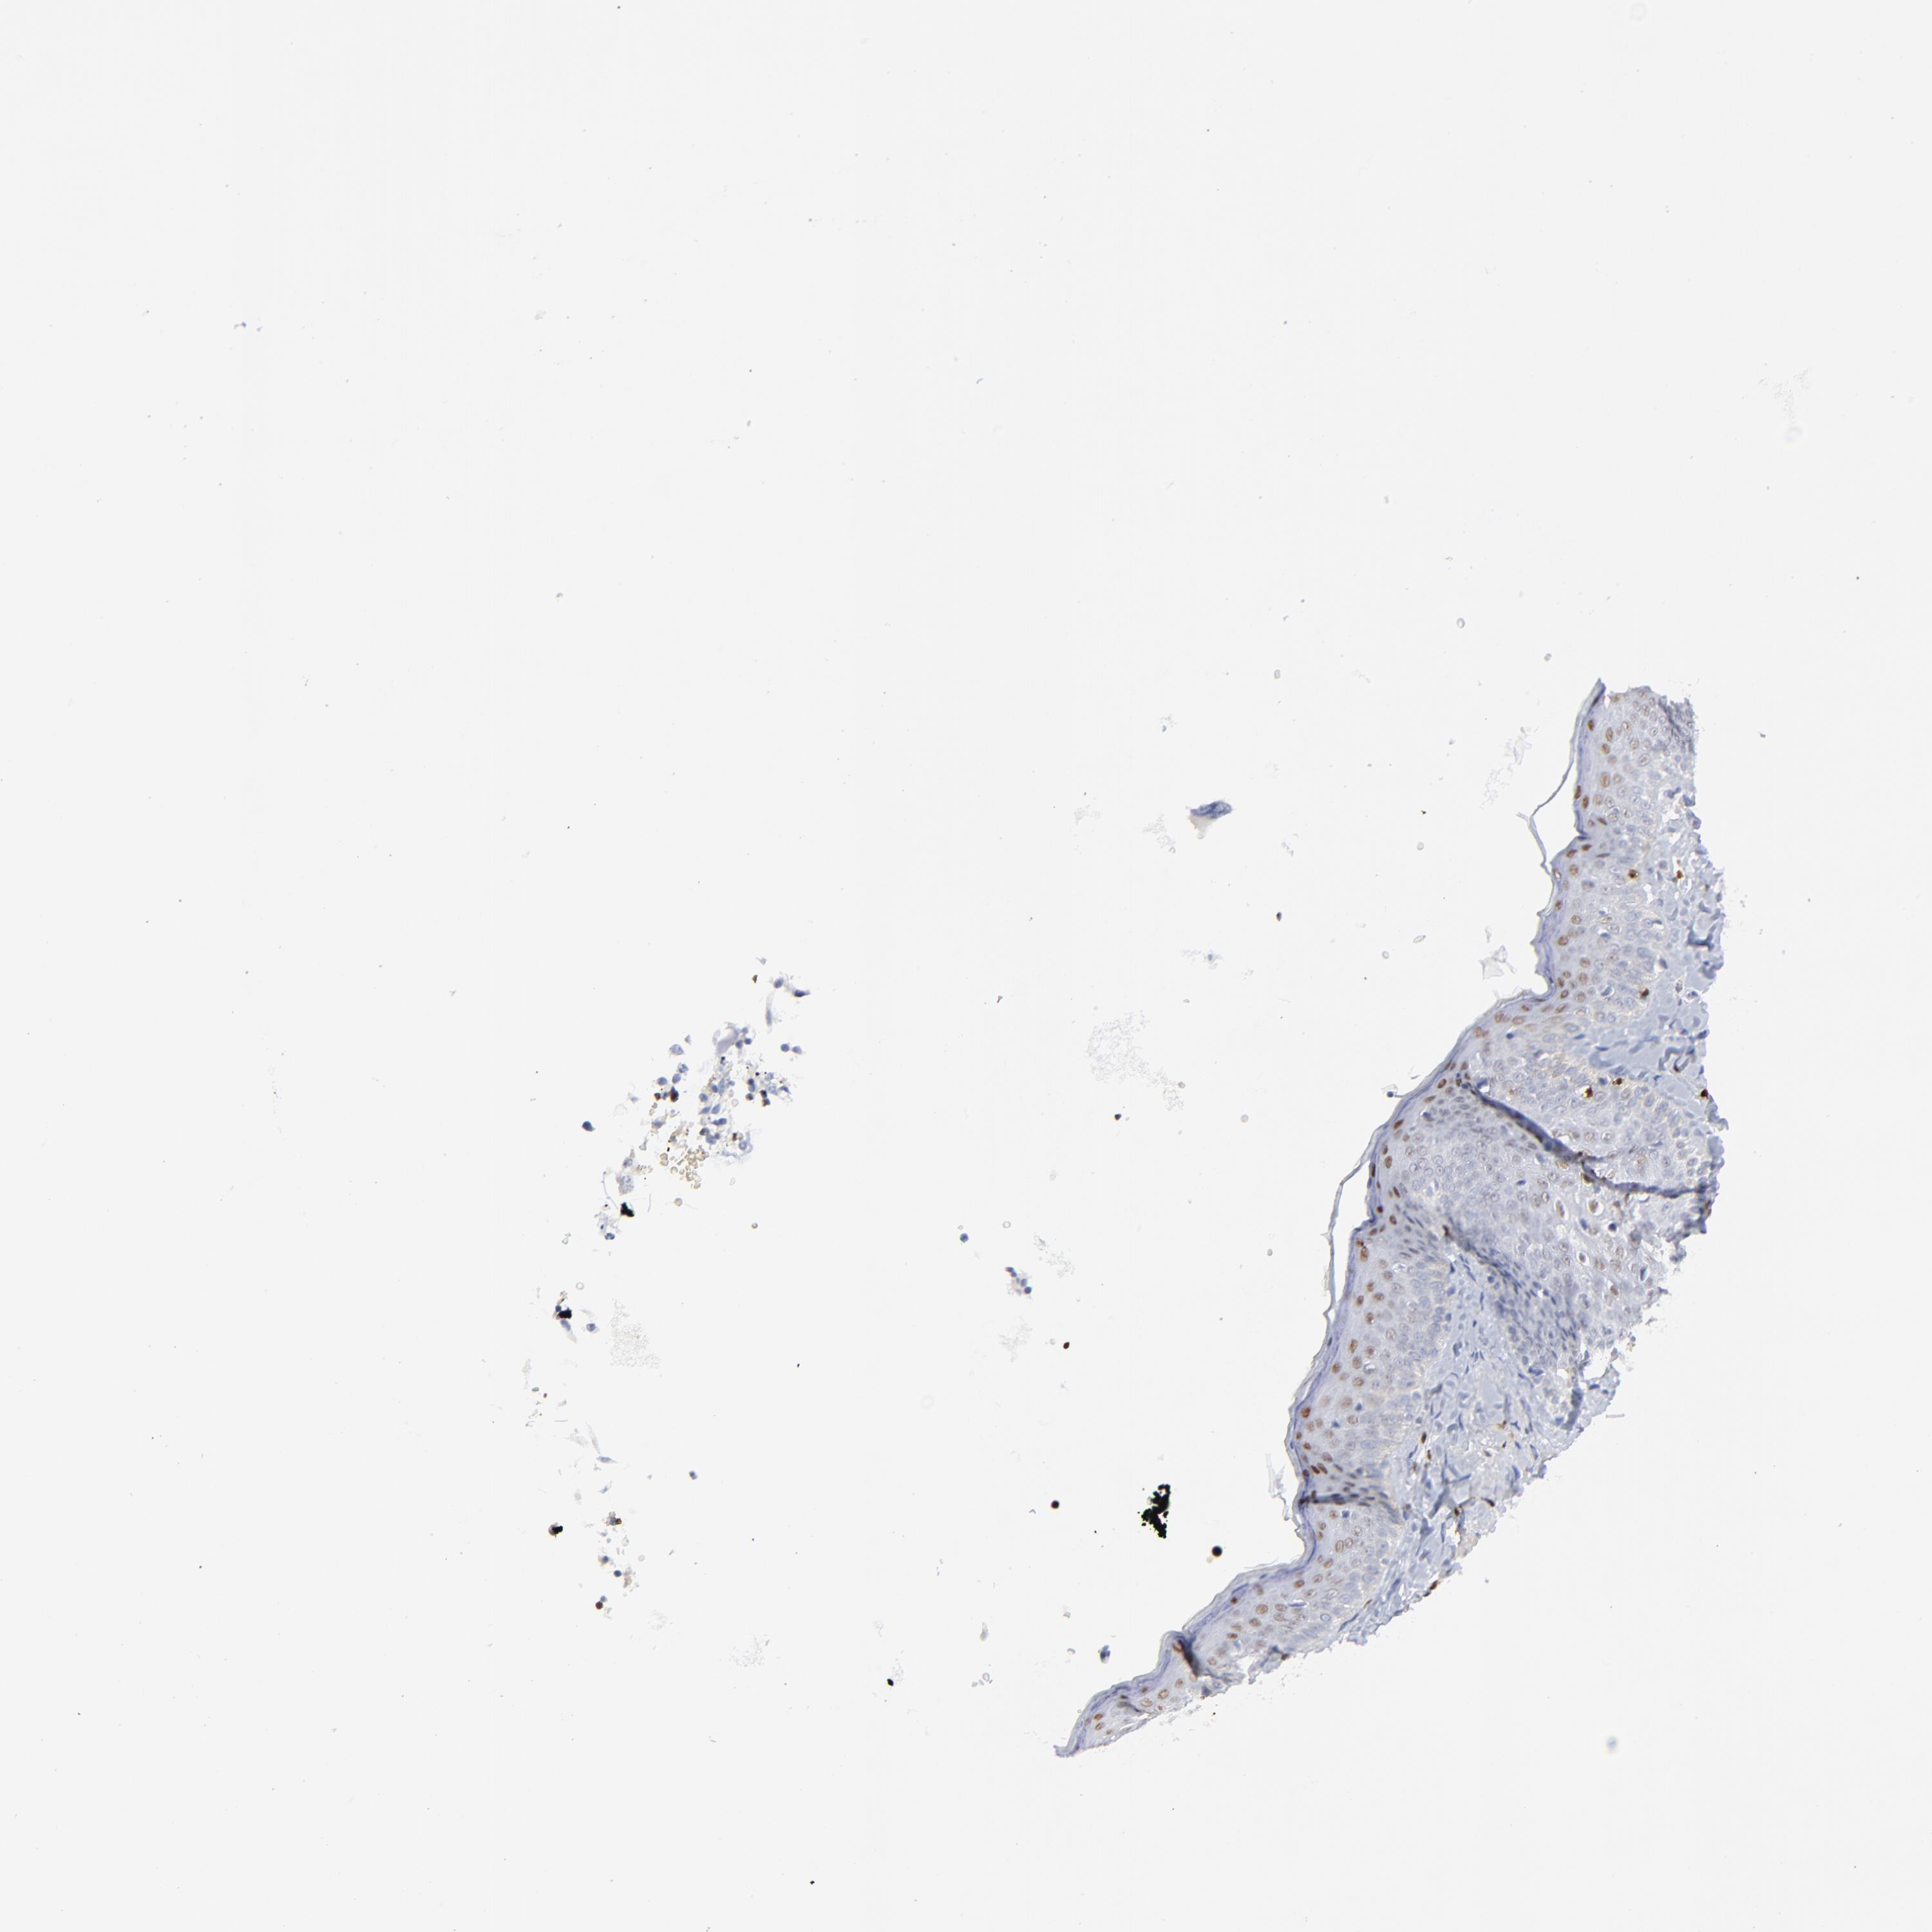

CANCER SKIN CANCER Show tissue menu

SKIN CANCER - Protein expressioni

A mouse-over function shows sample information and annotation data. Click on an image to view it in a full screen mode. Samples can be filtered based on level of antibody staining by selecting one or several of the following categories: high, medium, low and not detected. The assay and annotation is described here.

Antibody stainingi

Antibody staining in the annotated cell types in the current human tissue is reported as not detected, low, medium, or high, based on conventional immunohistochemistry profiling in selected tissues. This score is based on the combination of the staining intensity and fraction of stained cells.

Each image is clickable and will lead to virtual microscopy that enables deeper exploration of all samples and also displays staining intensity scores, fraction scores and subcellular localization as well as patient and tissue information for each sample.

Antibody CAB002625

Squamous cell carcinoma, NOS

Basal cell carcinoma